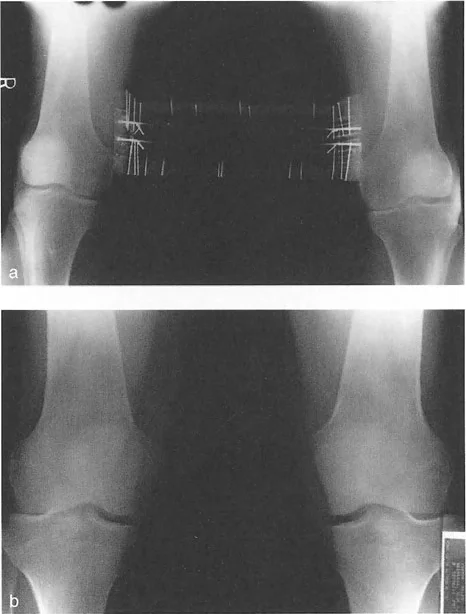

التصوير الإشعاعي المتقدم: مفتاح فهم التشوه

لا يمكن الحكم على المحاذاة والاتجاه بدقة إلا باستخدام صور الأشعة السينية الطويلة للطرف السفلي بالكامل في وضع الوقوف (فيلم بطول 51 بوصة). الأفلام التي تُؤخذ والمريض مستلقٍ أو أفلام الركبة القصيرة غير كافية تمامًا لتخطيط تصحيح التشوه.

نصائح مهمة للأشعة السينية الدقيقة:

- توجيه الرضفة: الدوران الصحيح للطرف أثناء الأشعة السينية أمر بالغ الأهمية. تكون الأشعة السينية صالحة فقط إذا كانت الرضفة متمركزة تمامًا بين لقمات الفخذ وموجهة للأمام مباشرة.

- وضع القدم غير ذي صلة: لا تضع المريض بناءً على زاوية تقدم القدم. إذا كان المريض يعاني من التواء في الساق للخارج، فإن وضع القدم للأمام سيؤدي إلى دوران داخلي للركبة، مما يبطل تمامًا قياسات مستوى التاج. دائمًا ما تُؤخذ الأشعة السينية بناءً على الركبة (الرضفة للأمام).

- ارتفاع الشعاع: يجب أن يتمركز شعاع الأشعة السينية عند مستوى مفصل الركبة من مسافة قياسية (عادة 10 أقدام) لتقليل أخطاء التكبير والتزيح.

انحراف المحور الميكانيكي (MAD): مقياس الضرر

عندما يؤدي تشوه المستوى التاجي إلى اختلال المحاذاة المحورية، فإن محور تحمل الوزن يمر إما وسطيًا أو جانبيًا لمركز الركبة. تُقاس القيمة المطلقة لهذا الانحراف باسم انحراف المحور الميكانيكي (Mechanical Axis Deviation - MAD).

كيفية قياس MAD:

- ارسم المحور الميكانيكي للطرف السفلي (خط مستقيم من مركز رأس الفخذ إلى مركز سطح الساق).

- ارسم قطعة خطية عمودية تمتد من خط المحور الميكانيكي هذا إلى المركز الهندسي الدقيق لمفصل الركبة (نقطة المنتصف بين شوكتي الساق).

- طول هذه القطعة العمودية، المقاس بالملليمترات، هو MAD.

يعكس حجم MAD بشكل مباشر حجم نقل الإجهاد المتغير عبر الركبة. يُعد قياس MAD متفوقًا بشكل كبير على مجرد قياس الزوايا الإجمالية للطرف لأنه يأخذ في الاعتبار التشوهات من أي نوع — بما في ذلك الدوران، الانتقال، والزاوية — ويترجمها إلى قيمة ميكانيكية حيوية واحدة ذات صلة سريريًا.